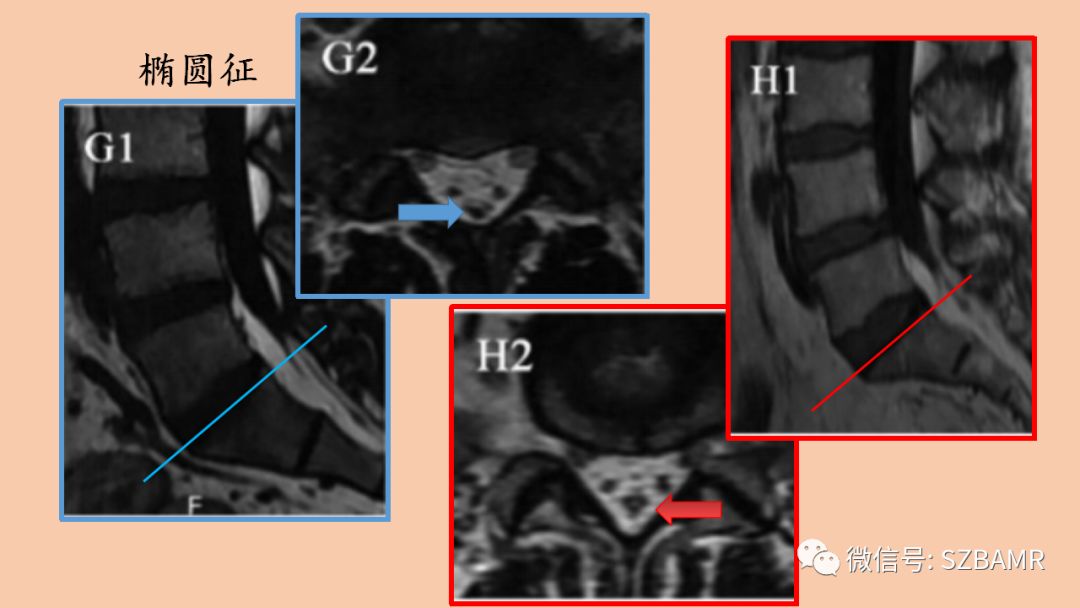

影像表现:胸椎通常堆积于椎管后方,腰椎包绕整个硬膜囊的脂肪信号,压迫硬膜囊,横断面上出现“Y字征”、“星形征”、“线征”或“椭圆征”。